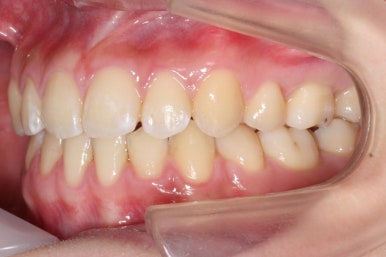

부산교정전문의 키다리아저씨치과에 처음 내원하셨을 때 당시의 입안 모습입니다.

윗니 뿐만 아니라 아랫니 부위에도 덧니가 관찰됩니다. 다른 앞니, 어금니 부위도 약간 삐뚤한 부분이 보입니다.